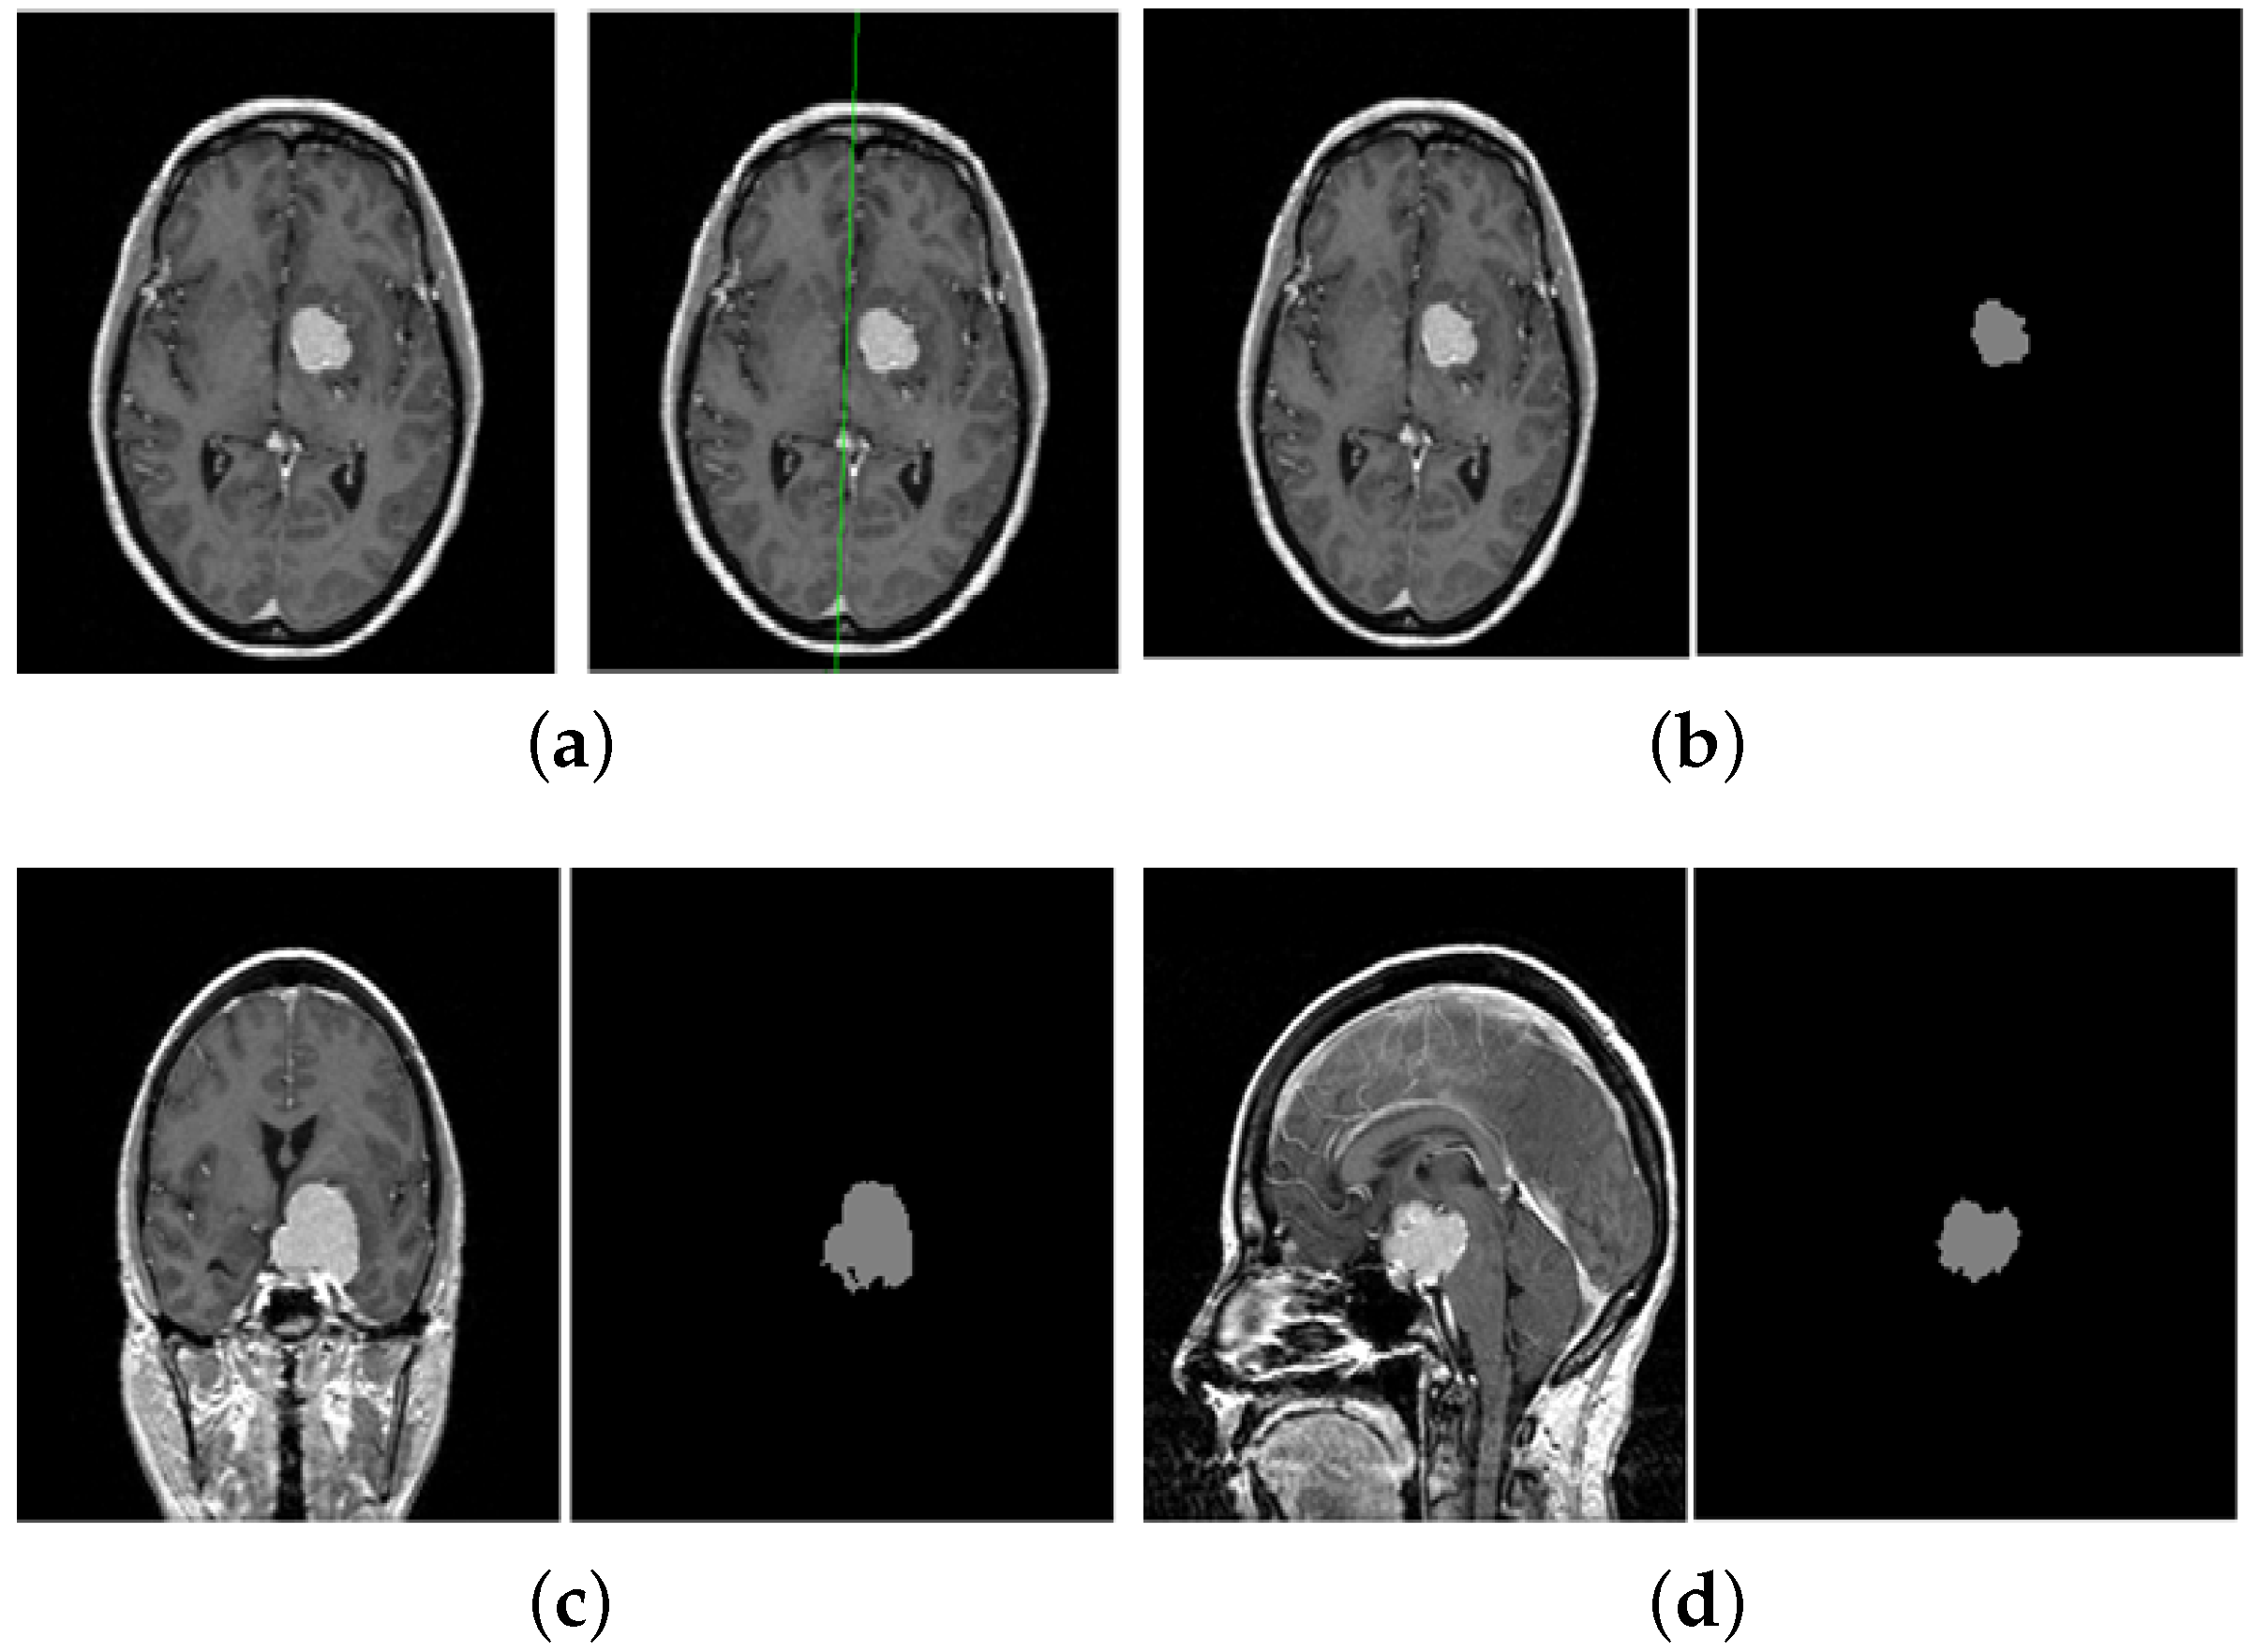

5. A Unified Framework for Brain Tumor Segmentation

- Bourouis, S.; Hamrouni, K. 3D segmentation of MRI brain using level set and unsupervised classification. Int. J. Image Graph. (IJIG) 2010, 10, 135–154. [Google Scholar] [CrossRef]